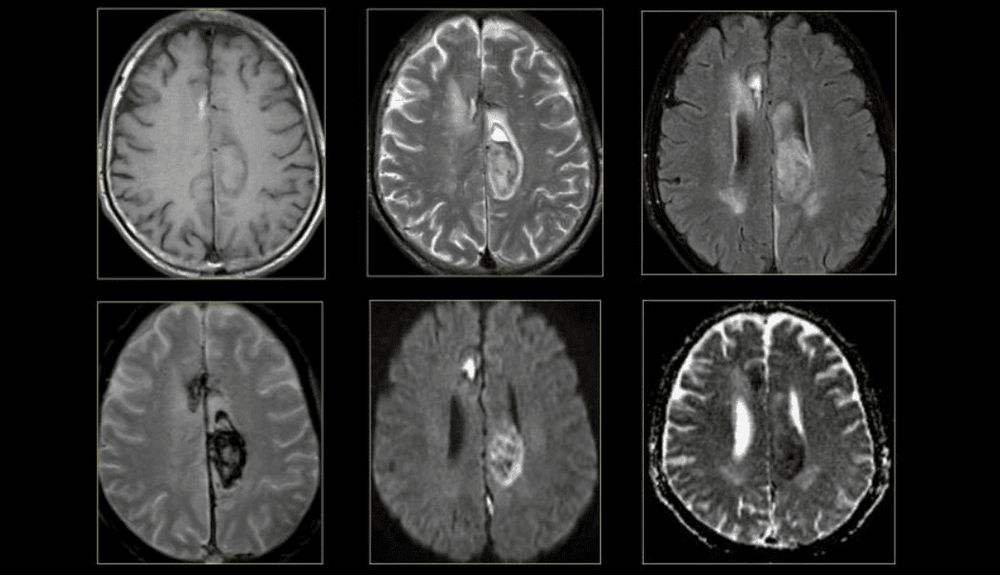

- Cộng hưởng từ phổ được chỉ định trong u não bao gồm: chẩn đoán phân biệt tổn thương do u hay không do u, gợi ý bản chất mô học. Phân biệt u não nguyên phát và thứ phát. Đánh giá sự lan rộng của u, tiến triển của u, đáp ứng điều trị, xác định vị trí lý tưởng để sinh thiết.

- Độ chính xác của cộng hưởng từ phổ trong chẩn đoán u và không u là 95-100%. Các dấu hiệu chính của u não trên cộng hưởng từ phổ là tăng choline, Cho/NAA, Cho/Cr, tăng lipid, lactate, giảm NAA, giảm NAA/Cr, giảm Cr.

- Chẩn đoán phân biệt u não và di căn não: khi không có đỉnh NAA và Cr trên phổ cộng hưởng từ, không tăng cho ở vùng gợi ý di căn não.

- Độ nhạy, độ đặc hiệu và độ chính xác của cộng hưởng từ phổ trong đánh giá độ ác cao và thấp của u não tương ứng là 100%, 86% và 96%. Các chất chuyển hóa dùng đánh giá độ ác của u là Cho, lactate, NAA, CR, mI.

- Xác định vị trí sinh thiết: Cộng hưởng từ phổ có khả năng xác định các vùng có Cho tăng cao nhất, vùng có hoạt tính u cao nhất đáy là các vị trí lý tưởng khi sinh thiết.

- Cộng hưởng từ phổ dùng trong đánh giá đáp ứng điều trị, xác định u tái phát, còn sót sớm hơn so với cộng hưởng từ thường quy, ngay cả khi bệnh nhân có lâm sàng cải thiện, phân biệt u tái phát, còn sót với các bất thường không do u sau điều trị. Khi Cho tăng hoặc có tỉ lệ Cho/NAA tăng gợi ý sau u tái phát.